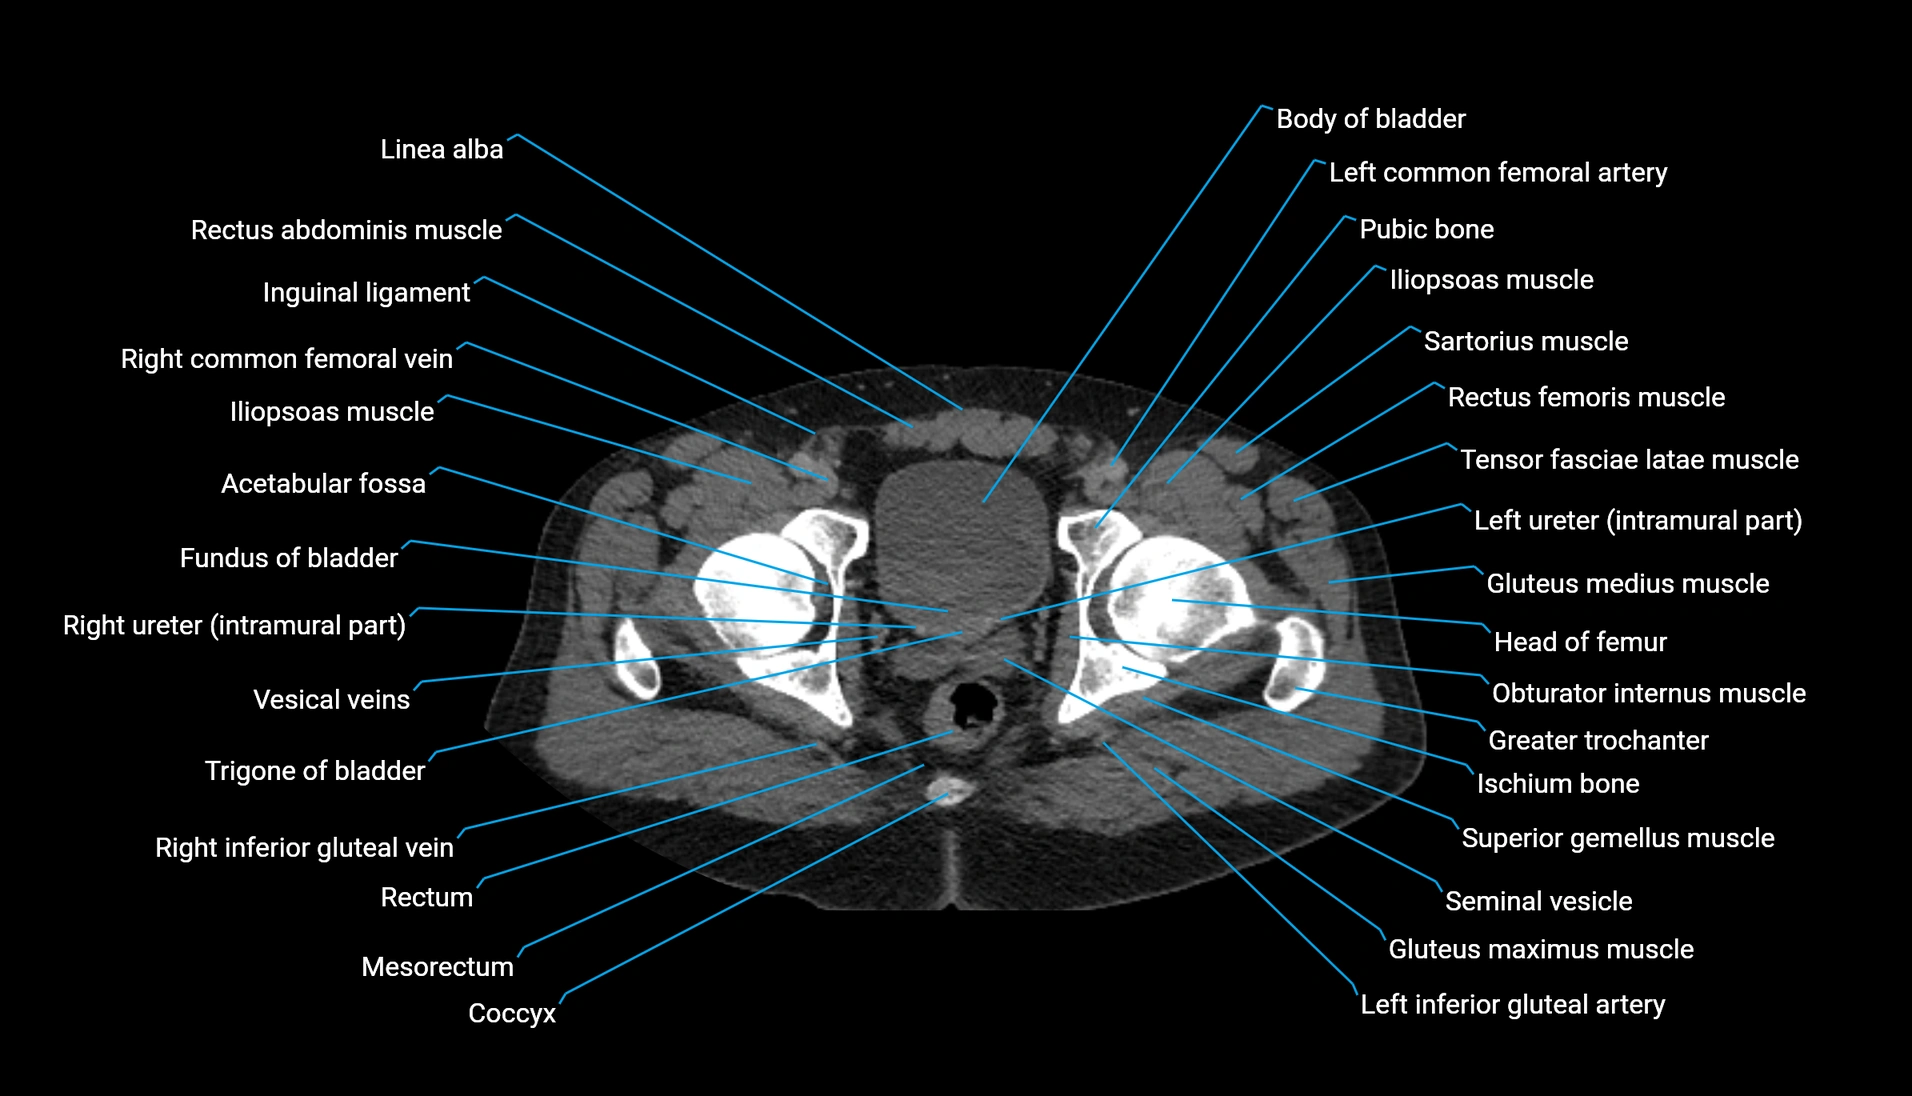

CT Appearance

Non-contrast CT:

-

Demonstrates cortical bone of acetabular rim in excellent detail

Detects fractures, dysplasia, retroversion, or bony overcoverage (pincer impingement)

3D reconstructions used in preoperative hip surgery planning

CT VRT 3D image

CT image